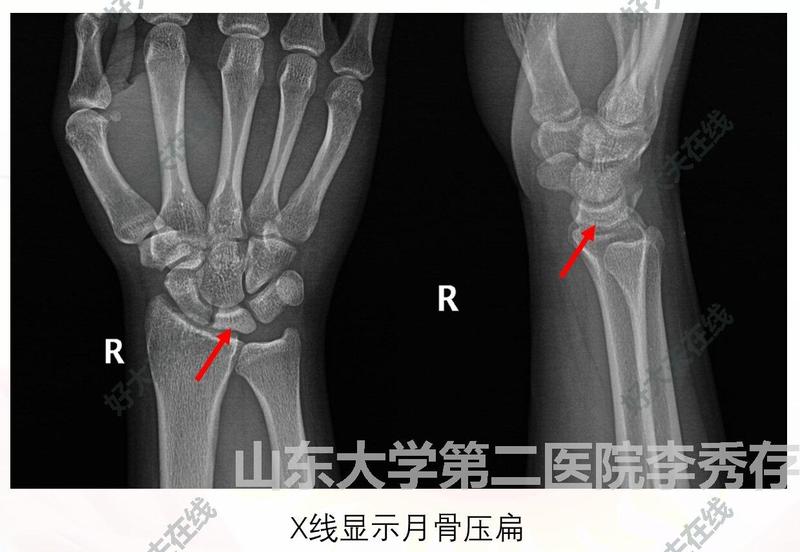

腕月骨缺血性壞死,又稱為Kienbock病,是月骨的缺血性壞死,可導(dǎo)致進(jìn)行性骨塌陷,進(jìn)而導(dǎo)致腕骨塌陷和繼發(fā)性骨關(guān)節(jié)炎。病因和病史不祥,但被認(rèn)為是一種慢行進(jìn)行性紊亂。月骨缺血性壞死是腕關(guān)節(jié)痛的主要病因之一。多發(fā)于20歲-40歲青壯年男性體力勞動(dòng)者,多為單側(cè)發(fā)病。以月骨缺血壞死為開始,繼發(fā)滑膜炎和創(chuàng)傷性關(guān)節(jié)炎。晚期造成手握力降低、腕關(guān)節(jié)頑固性疼痛和功能喪失。LichtmanⅠ期:月骨的形狀與密度正常,其診斷依賴于MRI。LichtmanⅡ期:月骨密度增高,但其形狀正常。LichtmanⅢ期:月骨出現(xiàn)塌陷,頭狀骨向近端移位。IIIA期,舟骨相對(duì)于其它腕骨的位置正常。IIIB期,舟骨半脫位導(dǎo)致舟骨環(huán)形征象。LichtmanⅣ期:出現(xiàn)繼發(fā)性橈腕關(guān)節(jié)炎,或全腕關(guān)節(jié)退行性改變。1.手術(shù)示意圖2.手術(shù)效果

月骨缺血性壞死

治療前右腕關(guān)節(jié)背側(cè)疼痛1年余,工作時(shí)疼痛加重。右腕關(guān)節(jié)屈伸活動(dòng)受限,旋前選后活動(dòng)度未見異常改變。該患者為裝修工人,年輕患者。術(shù)前診斷:右腕月骨缺血性壞死(IIIA期)。治療后治療后即刻治療:微創(chuàng)手術(shù)治療——關(guān)節(jié)鏡下頭狀骨短縮截骨空心螺釘內(nèi)固定術(shù)